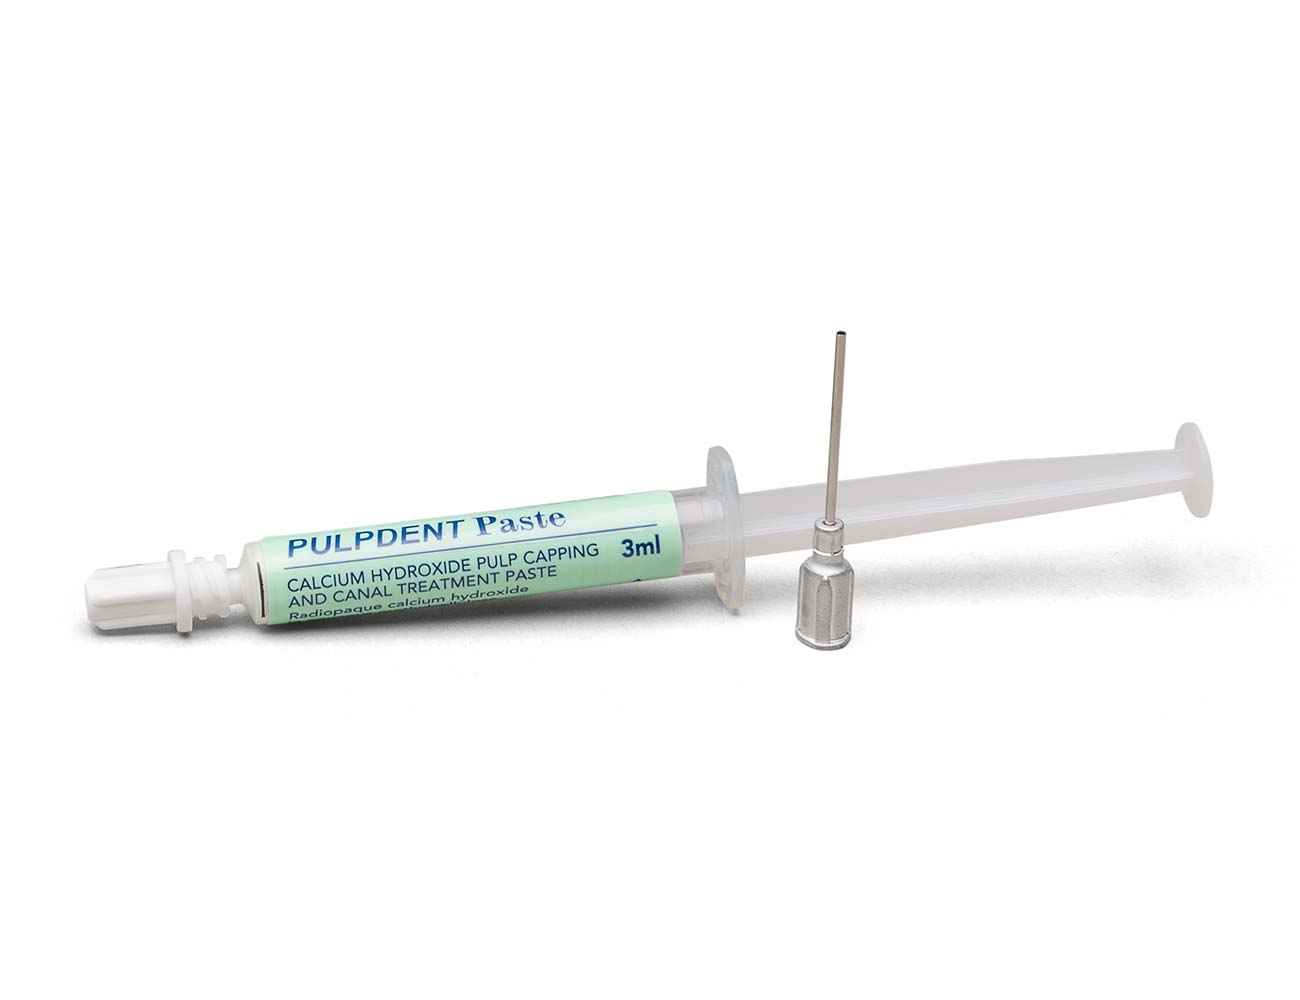

Pulpdent Paste is the original premixed calcium hydroxide methylcellulose pulpal dressing. It is indicated for direct pulp capping, pulpotomy and pulpal curettage procedures, and it is used routinely as an intracanal dressing between office visits and when extended calcium hydroxide therapy is indicated.

PSYK – Pulpdent Paste Kit: 3 mL syringe + 24 needles (18 gauge blunt)

PSY – Pulpdent Paste: 3 mL syringe

PSYN – Pulpdent Paste syringe needles, Pkg. of 24

A: Pulpdent Paste, the original calcium hydroxide aqueous-methylcellulose pulpal dressing, is a thick paste. It is packaged in a standard 3 mL push syringe and is available in the syringe alone or in a kit with 18-gauge x 1” dispenser needles. TempCanal is a lower viscosity paste packaged in a 3 mL screw syringe. It is available in the syringe alone or in a kit with 22-gauge and 25-gauge x 1.25” dispenser needles. Multi-Cal is a creamy consistency paste, similar in viscosity to TempCanal, and it is available in a standard 3 mL push syringe or in a kit with 4 x 1.2 mL syringes + 22-gauge x ½” applicator tips. Forendo Paste is a creamy paste packaged in a 2.2 gm push syringe with 22-gauge x ½” applicator tips.